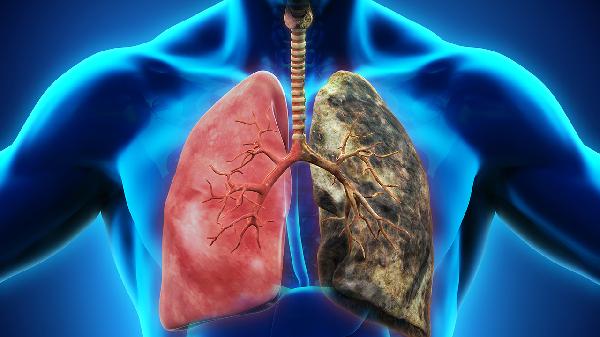

1、长期吸烟者

每天1包烟持续20年以上的人,肺癌风险是不吸烟者的10-20倍。即使已戒烟,风险仍会持续10-15年。